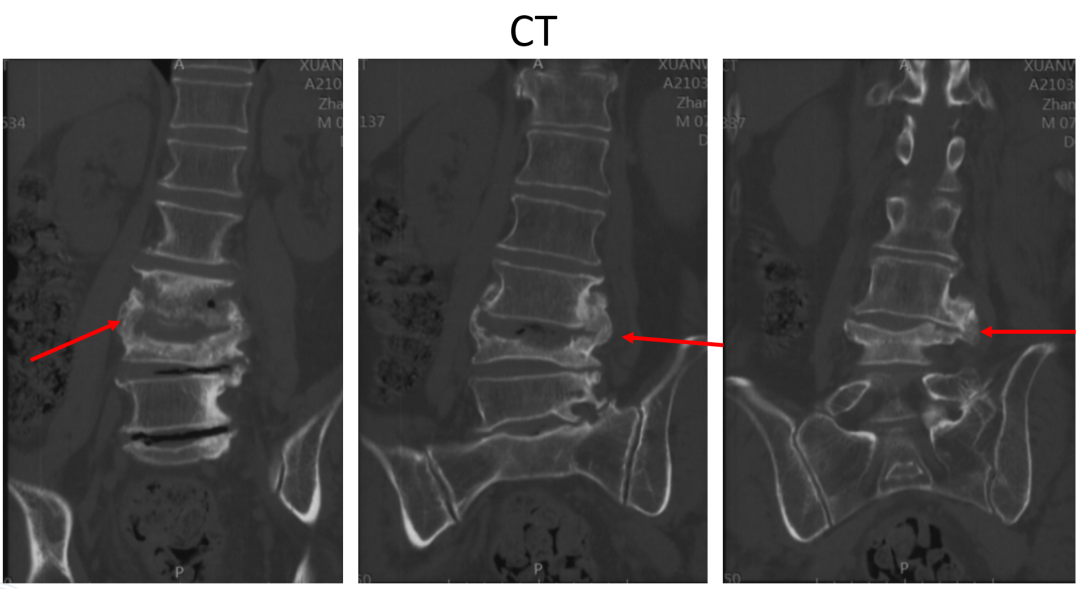

讨论主题:L4压缩骨折伴脊柱侧后凸畸形

影像资料:

腰椎侧后凸畸形

腰椎陈旧性压缩性骨折(L4)